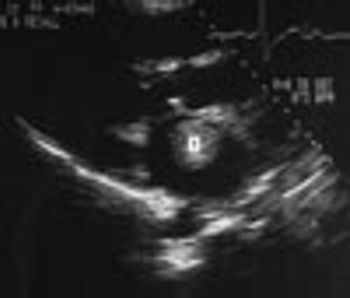

A 72-year-old man with a history of rheumatic heart disease presented with pulmonary congestion and syncope. Results of the cardiac examination suggested mitral stenosis and atrial fibrillation with a controlled ventricular response. Two-dimensional echocardi-ography revealed a large, free-floating ball thrombus (T) in the dilated left atrium and demonstrated rheumatic and severely stenotic mitral valve leaflets.